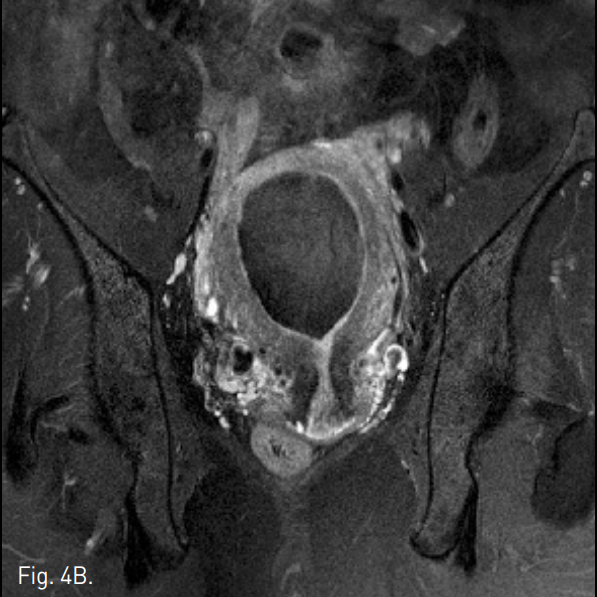

Fig. 4

A-C. Three months follow-up T2-weigh ted transverse (A), coronal (B), sagittal (C) MR images show a huge mass of low signal intensity.

D. Three months follow-up T1-weighted MR image with contrast enhancement shows a non-enhancing uterine mass.